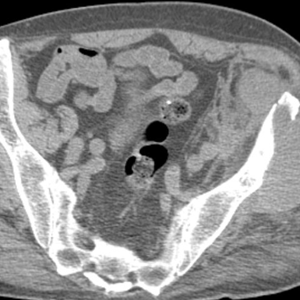

Caso 2 | Abril 2026 | Hospital Italiano

Masculino. 73 años. MC: Dolor unilateral en miembro inferior izquierdo de larga evolución (2 meses) que empeora los últimos días. […]